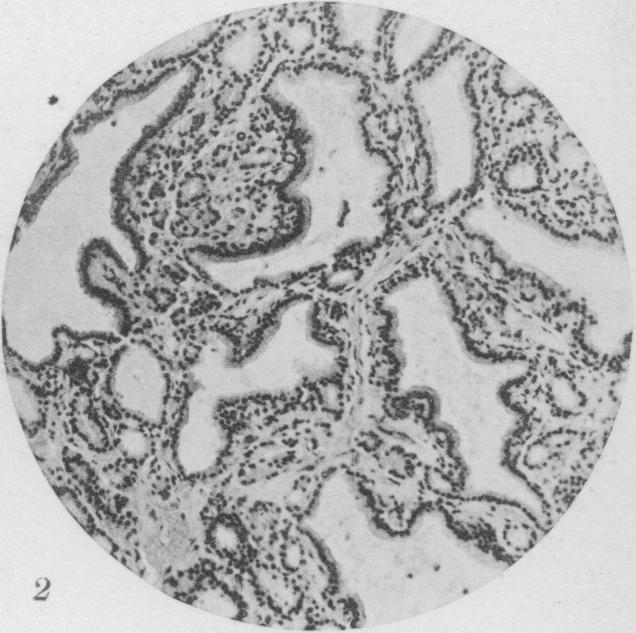

Benign Epithelial tumors of the Thyroid Gland.

J Med Res. 1913 Jan;27(3):229-268.5.